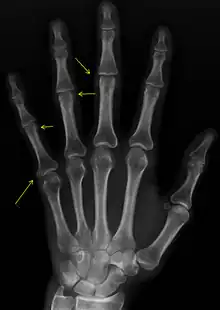

| CREST syndrome (calcinosis and sclerodactyly) | |

Sclerodactyly

Though it is the most easily recognizable manifestation, it is not prominent in all patients. Thickening generally only involves the skin of the fingers distal to the metacarpophalangeal joints in CREST. Early in the course of the disease, the skin may appear edematous and inflamed. Eventually, dermal fibroblasts overproduce extracellular matrix leading to increased tissue collagen deposition in the skin. Collagen cross-linking then causes a progressive skin tightening. Digital ischemic ulcers commonly form on the distal fingers in 30–50% of patients.[3]